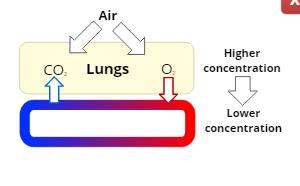

Respiration

the exchange of oxygen and carbon dioxide in the body

External Respiration

the exchange of the gases, oxygen and carbon dioxide, between the air in the lungs and the bloodstream